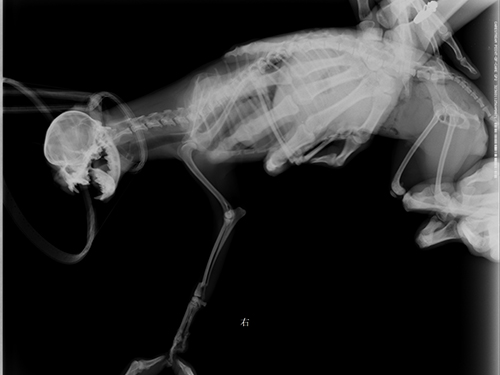

图5:完全康复后

主诉:该犬从椅子上跳落后右前肢不能着地,稍有碰触即疼痛惨叫。CR显示该犬右前肢桡尺骨骨折,经协商后实施骨折内固定手术。三周后着地,走路无异常。一个月后痊愈。